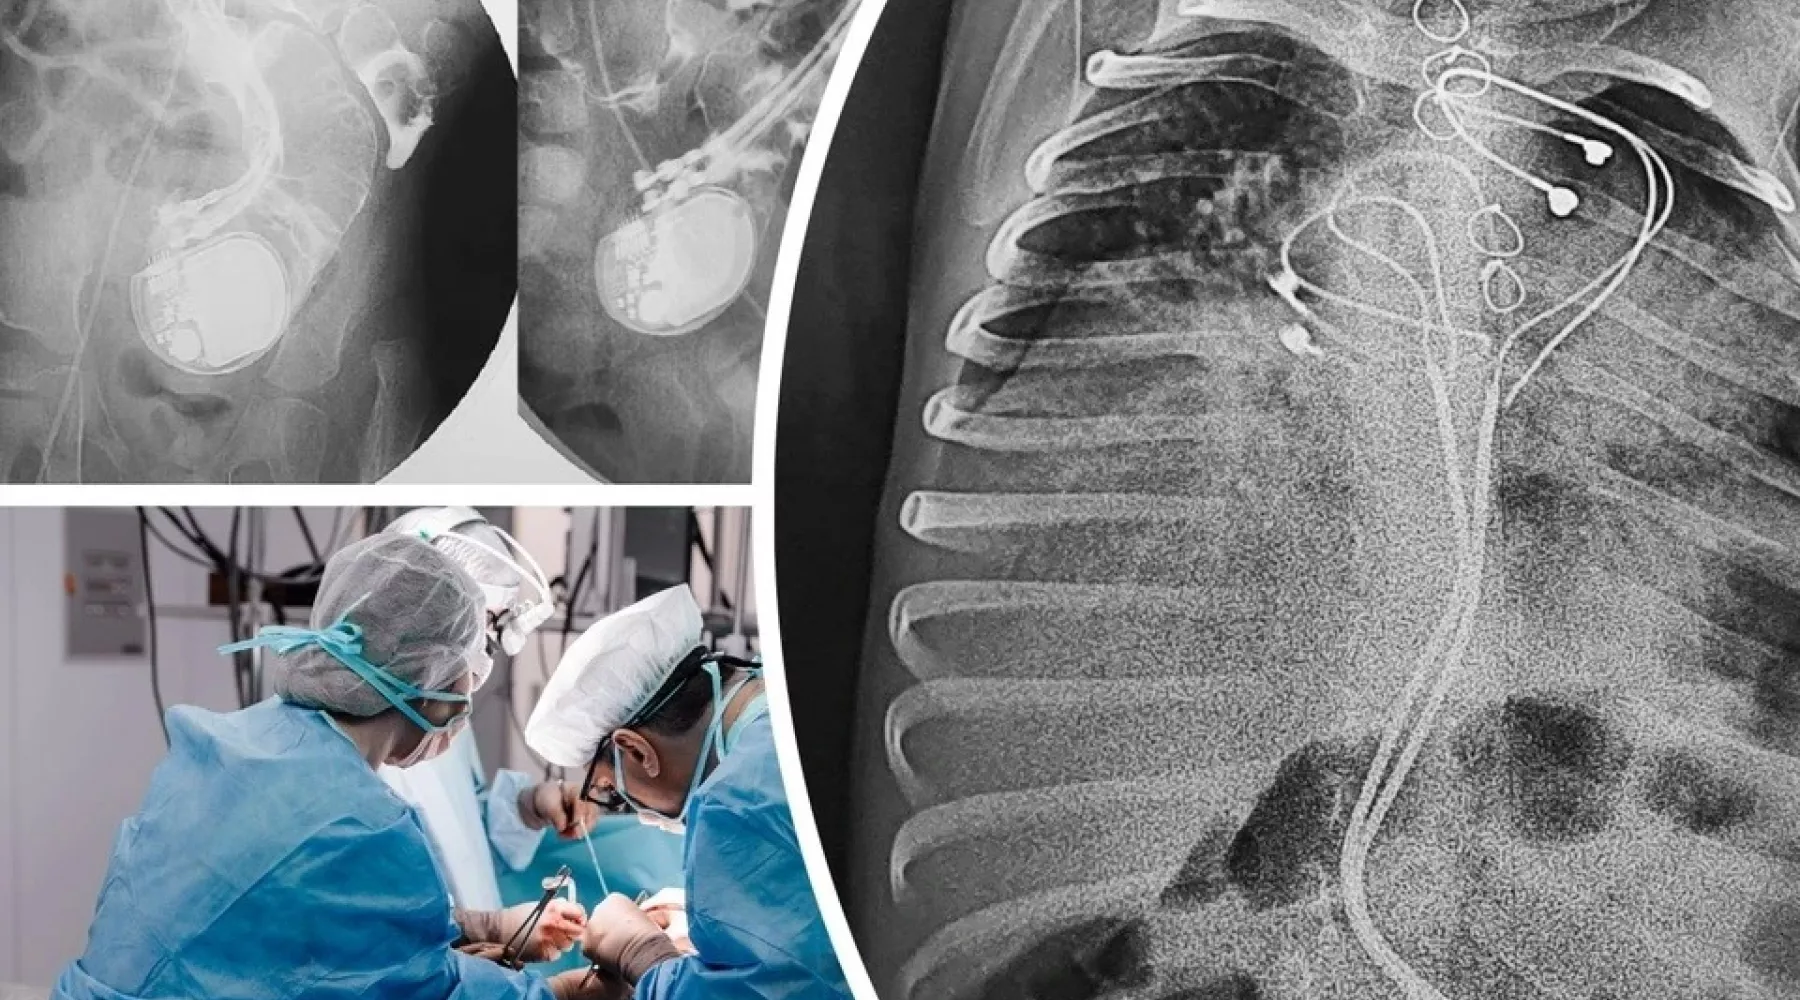

Хирурги клиники Мешалкина и Новосибирской областной больницы спасли 3-летнего ребенка с кардиостимулятором в кишечнике. Ребенок родился с редкой жизнеугрожающей аритмией, которая встречается у 1 из 25 тысяч новорожденных. Ему установили кардиостимулятор, который буквально всосался в живот, сообщает «КП-Новосибирск» .

— Из-за малого размера тела малыша кардиостимулятор не получилось установить в грудную клетку, как взрослым пациентам. Поэтому его разместили в верхней части живота, поверх брюшины и прямой мышцы. Электроды прикрепили к правому предсердию и верхушке правого желудочка, — объяснили в НМИЦ им. ак. Е.Н. Мешалкина.

Через три года мальчика привезли в больницу Барнаула с высокой температурой и симптомами кишечной непроходимости. Кардиостимулятор в месте имплантации не прощупывался, а на рентгене выяснилось, что устройство проникло в кишечник. Там оно продолжало исправно работать и задавать ритм сердцу.

— Кардиохирурги Тимур Хапаев и Сергей Иванцов имплантировали однокамерный кардиостимулятор в грудь, а хирурги Владислав Цыганок и Юрий Койнов извлекли устройство, отсекли инфицированные электроды и закрыли дефект кишечной стенки. После курса антибактериальной терапии на десятый день ребенок был выписан в удовлетворительном состоянии, — рассказали в новосибирской клинике.